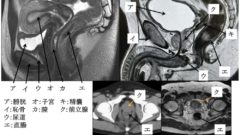

総腸骨動脈

(75am53、72am61、69am91)

・総腸骨動脈→外腸骨動脈+内腸骨動脈

・外腸骨動脈→大腿動脈

・内腸骨動脈→子宮動脈